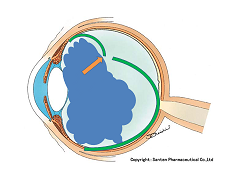

写真だと水色の部分が視神経乳頭(マ盲点)になります。ちなみに、物を見る中心部の網膜は黄斑と呼ばれ、オレンジの矢印に当たります。

マリオット盲点以外の部位が欠ける場合は病気となるのですが、視野が欠ける代表的な疾患として、緑内障があります(日本人の失明の原因の第一位)。